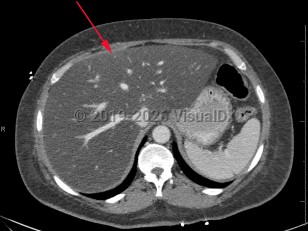

Screening for MASLD is of the utmost importance in patients with underlying risk factors, primarily obesity and metabolic syndrome, as it is often asymptomatic. American Diabetes Association (ADA) guidelines recommend routine MASLD screening in patients with diabetes and prediabetes. Some patients report vague symptoms such as fatigue or mild right upper quadrant abdominal pain. If MASLD progresses to cirrhosis, patients will often present with signs and symptoms of advanced liver disease: spider angiomata, gynecomastia, ascites, jaundice, and peripheral edema. Cardiovascular disease is the leading cause of death in persons with MASLD.